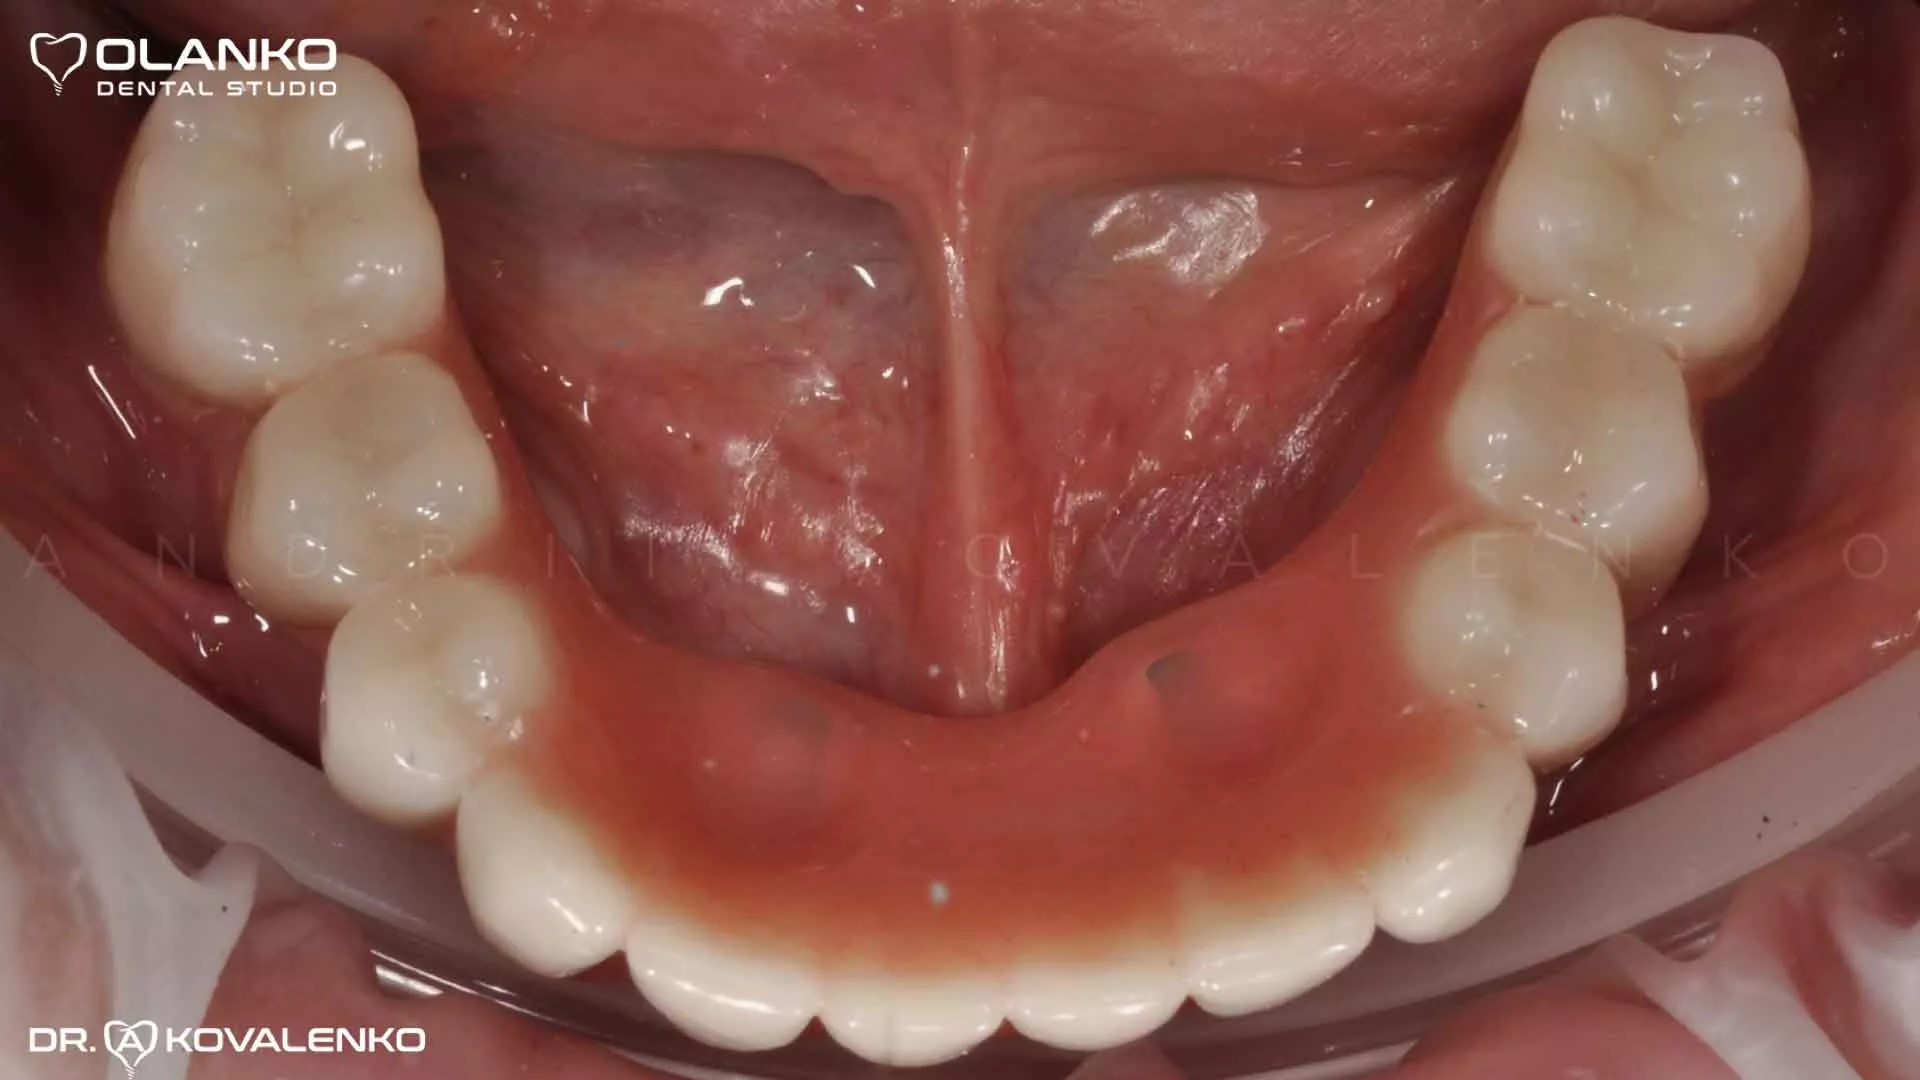

Фото вид зубных имплантатов после приживления

Клинический случай 9 имплантация зубов